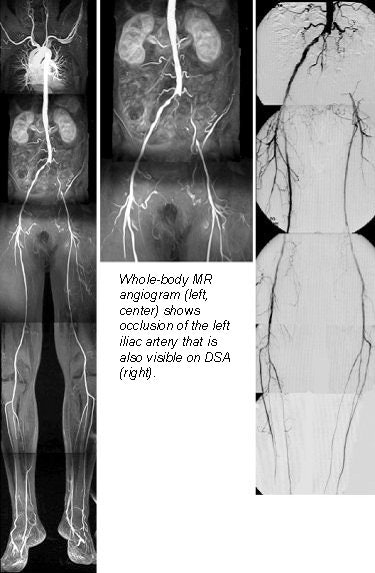

A new rolling-platform table could make whole-body MR angiography fast and practical for the first time, according to Dr. Mathias Goyen, a radiologist from University Hospital Essen in Germany. AngioSURF's ability to reduce procedure times and increase anatomical coverage has made it popular with both patients and clinicians at the university's MR center, where the table was developed.

In two studies presented at last month's European Congress of Radiology, Goyen and colleagues evaluated AngioSURF's performance, and sought to determine the optimal contrast dose needed to detect pathology in the peripheral vessels. Users of the system were not only able to detect significant pathology, but its longer coverage helped them find unsuspected disease as well.

"Recently, whole-body MR angiography has become possible by combining the contrast-enhanced MRA approach with the latest high-performance gradients," Goyen said. "We are now able to (image) the arteries from the carotids down to the runoff vessels in a single exam. Our preliminary results are quite promising, with sensitivities and specificities for detecting stenoses and occlusions in the mid-80s up to the mid-90s."

The first study examined 3 healthy volunteers, as well as 10 patients with angiographically documented peripheral vascular disease. The patients had all undergone digital subtraction angiography (DSA) within the previous 72 hours. Evaluation of the AngioSURF system was based on a total of 214 vascular segments for which DSA was available for comparison.

The results were based on 214 vascular segments in which DSA was available for comparison. All patients tolerated the exams well, and all exams were of diagnostic quality, showing complete correlation with DSA findings, Goyen said. For the detection of significant stenoses, the AngioSURF procedures had a sensitivity of 95.3% and specificity of 95.2% compared to DSA.

"The AngioSURF system allowed the accurate display of arteriovasculature from the supraaortic arteries to the lower extremity vessels," Goyen said. "Due to the extended coverage that's provided, we found additional findings that may be relevant to the treatment and diagnosis of vascular disease."